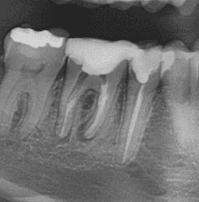

Achados radiográficos radilúcidos:

Achados radiolúcidos em radiografias podem ser indicativos de várias condições que afetam a saúde bucal e precisam ser considerados e avaliados antes de realizar movimentações ortodônticas. Alguns achados mais comuns são:

Cáries: Devem ser tratadas antes do início do tratamento ortodôntico, para evitar complicações, uma vez que a progressão da cárie pode afetar a estrutura dentária e saúde periodontal.

Lesões periapicais: Devem ser tratadas adequadamente com endodontia antes do início da ortodontia e acompanhamento radiográfico.

Cistos: A presença de cistos pode interferir os movimento ortodônticos e a saúde bucal em geral. O tratamento ortodôntico pode ser contraindicado até que a condição seja resolvida, geralmente com cirurgia ou outros tratamentos médicos.